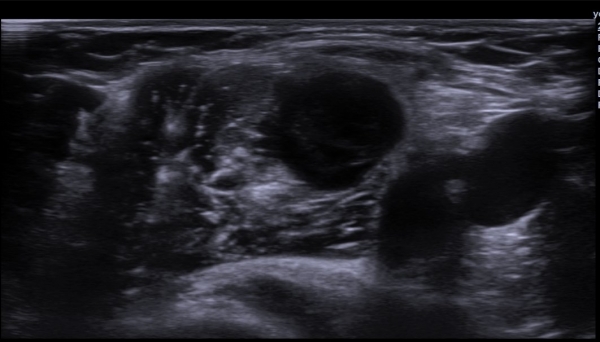

¼â°ñ¾Æ·¡¿¡¼­ »ó¿Ï½Å°æÃÑ Á¾´Ü¸é°Ë»ç¿¡¼­ »ó¿Ï½Å°æÃÑ ¿ÜÃø ²ö(lateral cord)ÀÇ Àú¿¡ÄÚ ºÎÁ¾ÀÌ

°üÂûµÈ´Ù(»çÁø 7).